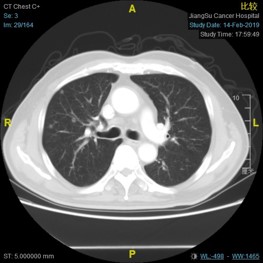

2017-8-20行FOLFIRI+西妥昔单抗治疗4周期。

2017-10-20:CEA 12.19 ng/ml

2017-12-19:CEA 5.28 ng/ml

Q3 下一步如何治疗:

C225+FOLFIRI

C225+单药化疗

C225

口服化疗

维持治疗(C225+IRI)

2018-3-8:CEA 4.89 ng/ml